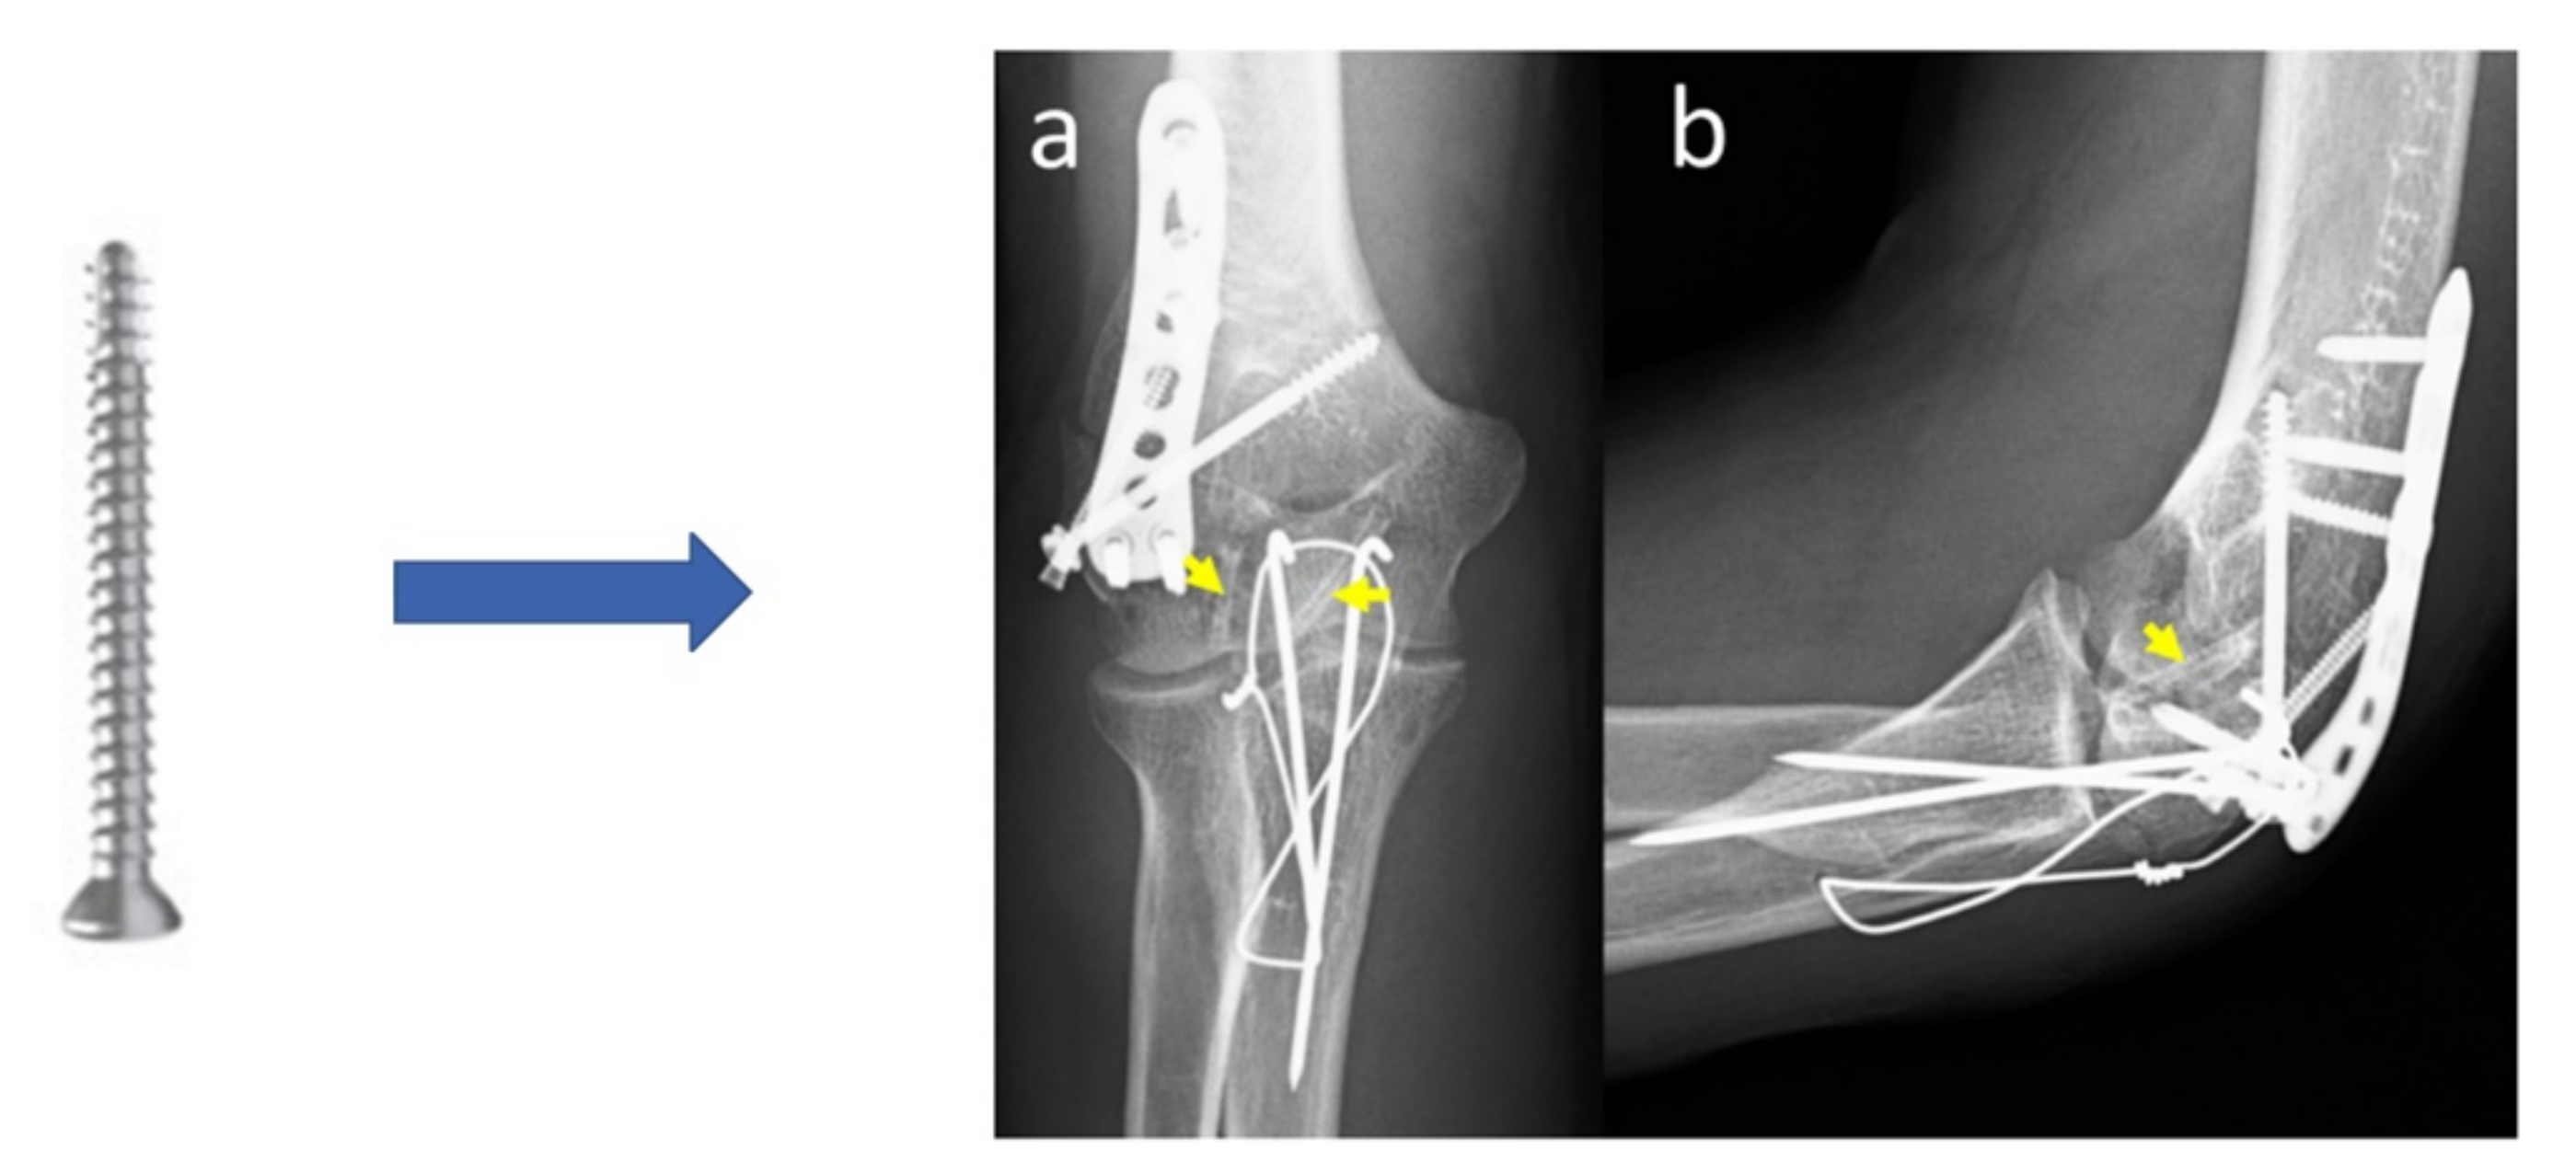

- Lam, W.-H.; Tso, C.-Y.; Tang, N.; Cheung, W.-H.; Qin, L.; Wong, R.M.-Y. Biodegradable Magnesium Screws in Elbow Fracture Fixation: Clinical Case Series. J. Orthop. Trauma Rehabil. 2021. [Google Scholar] [CrossRef]

| Elbow fracture | 2.7 mm diameter screws | Mg-Y-RE-Zr (MAGNEZIX®, Syntellix AG) | Human female 48 years old (2020) | [24] |